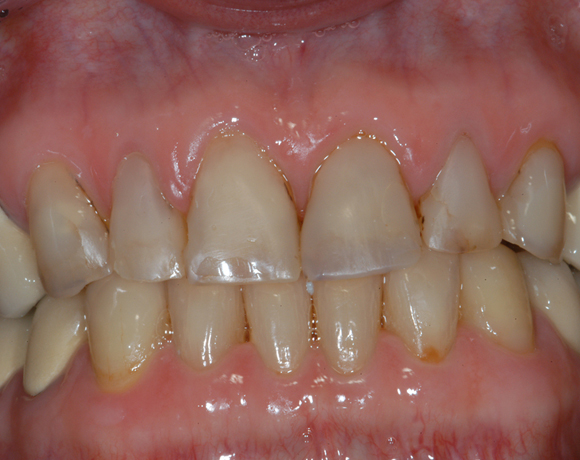

22 Einzelkronen mit Eris for E II

Empress II Presskeramik mit Eris Verblendkeramik bei einer Neuversorgung im Oberkiefer komplett und im Unterkiefer Vollkronen auf den Seitenzähnen.

Ein Projekt aus dem Jahr 2004

Hier wurden der ganze Oberkiefer und die Seitenzähne im Unterkiefer mit neuen Kronen aus Empress 2 und mit Eris Verblendkeramik versorgt.